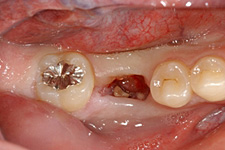

第一大臼歯の抜歯後2週間で移植を行いました。

移植のために抜歯された右下の親知らず。歯根がまだ完成していない若い歯です。

移植直後

移植直後。歯根がまだ完成していない歯では、根の先が開いていることに気づきます。